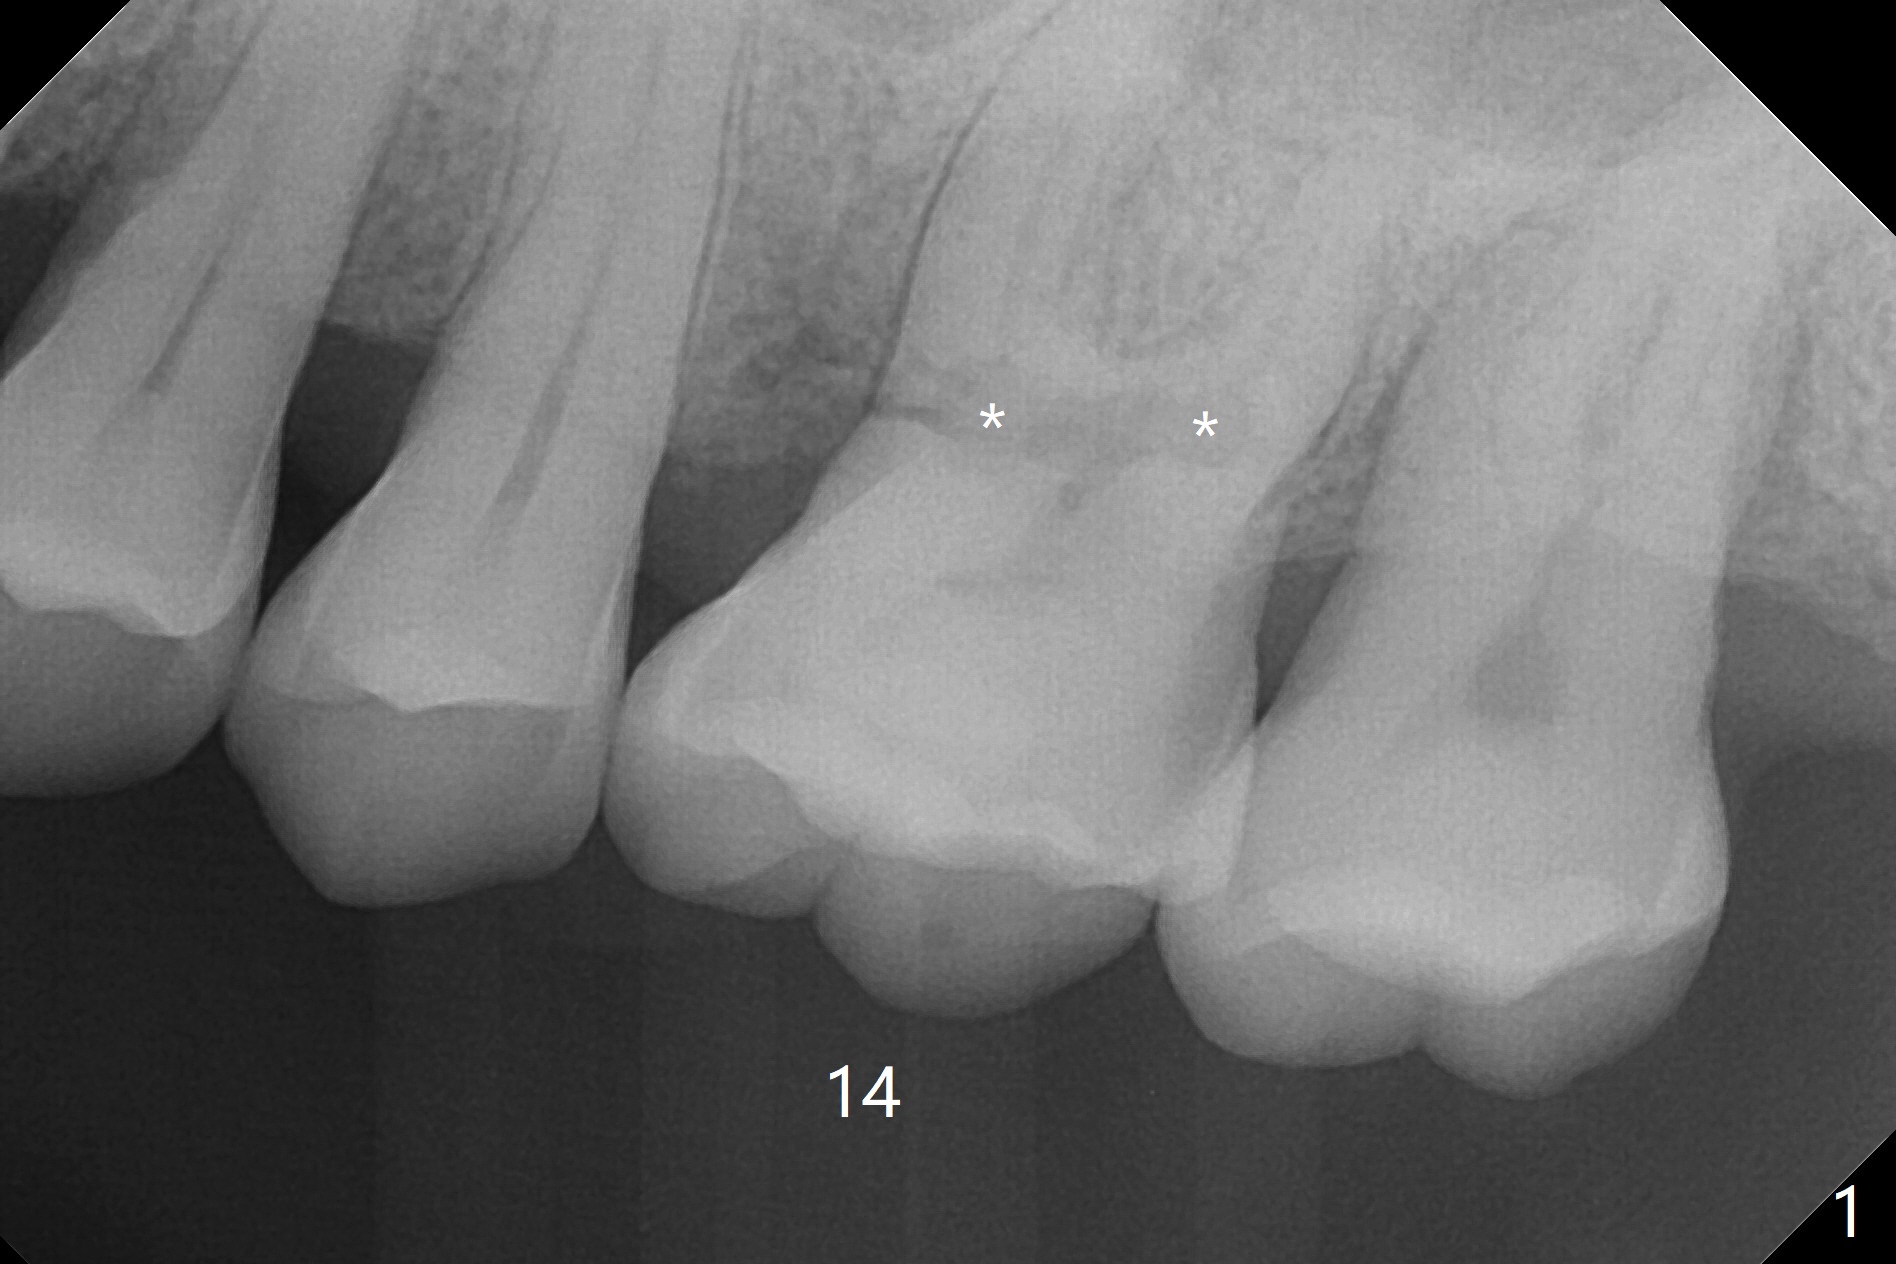

A 60-year-old man had buccal furca abscess at #14 with an unknown radiolucent lesion within the tooth five months earlier (Fig.1 *). Now the tooth is sensitive to cold. CBCT shows internal resorption involving the mesiobuccal and distobuccal roots (Fig.3,4 (axial section) *) with exits mesially (Fig.3 >) and buccally (Fig.2 ^). There is periapical radiolucency of MB (Fig.3,7) with the thickened overlying sinus membrane (Fig.3,5,6 (*), as compared to that over the tooth #3 (Fig.6)). Osteotomy will be established in the septum away from the lesion (Fig.8 red circle) and for 5 mm (Fig.5 (coronal section)). He is a heavy bruxer, loosening Ketac-cemented unipost. Use PRF to repair the defect associated with the MB lesion and sinus lift.